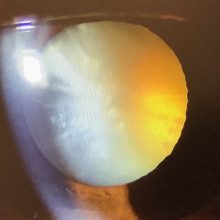

今日、右眼の白内障の手術の申し込みをいただいた70代半ばの男性の方は、約15年前に右眼のぶどう膜炎を発症し、ずっと治療を継続されていたそうです。ぶどう膜炎というのは、眼の中のぶどう膜という組織に炎症を起こす病気で、治療はステロイドで炎症を抑えることが必要になります。炎症が起こることでも白内障は進む方向に影響が出ることもありますが、ステロイドも白内障を進めてしまう作用があります。そのため、ぶどう膜炎を起こすと、白内障が進んでしまうことがあります。ただ、ぶどう膜炎に限らず、ステロイドを処方しようとすると、白内障(や緑内障)を心配して、ステロイドを使いたくないとおっしゃる方もいて、どうしても使わなくてもよい場合は、無理に使うこともありませんが、短期間、適切な量のステロイドを使うことは問題にならないですし、ステロイドを使ってしっかり炎症を抑えることも治療上、必要なことなので、あまり心配し過ぎずに適切な治療をすることは大事なことだと思います。

結果として、ぶどう膜炎で白内障が進むことはありますが、その時は今回の患者さんのようにきちんと治療をしてあげればよいかと思います。白内障はちょっと進んでいましたが、しっかり手術したいと思います。